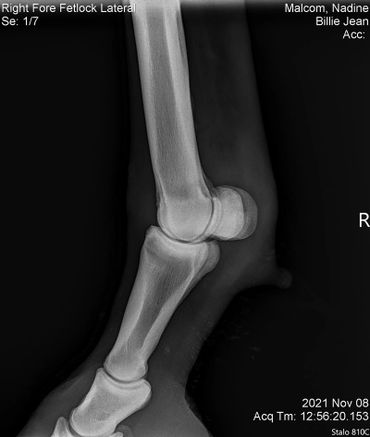

The only issue I'm still working on with her is that she still doesn't like to have a saddle put on her back. Once it's on she's good to go. I've had this mare checked for everything! She got scoped for ulcers, checked for kissing spine, her knees x-rayed since she's a little over the knee and her coffin/ fetlock x-rayed. She's totally fine! I assume that this poor girl was probably ridden in a really poor fitting saddle for years which brought her great uncomfort. I believe over time she will eventually get over this but I can't stress enough that patience is required while saddling her!

BJ also had hr knees, fetlock and coffin joint x-rayed on July 7, 2022. Her vet bill was $185.

We did a full wellness and lameness exam and everything looked pretty good. She showed some soreness in her right front fetlock so we did some x-rays but nothing really to see that would raise concern. We also did x-rays on her stomach and it showed she has some sand which we have been treating with Sand Clear.We didn't do x-rays on her knees. Dr. Johnson said she's probably got some fluid in there because it looks like she used to hit her knees on something a lot so we are rubbing some DMSO on it to relieve some of the swelling.Billie Jean also got a dental float. After examining her teeth closer it turns out she is more like 18-20 years old.